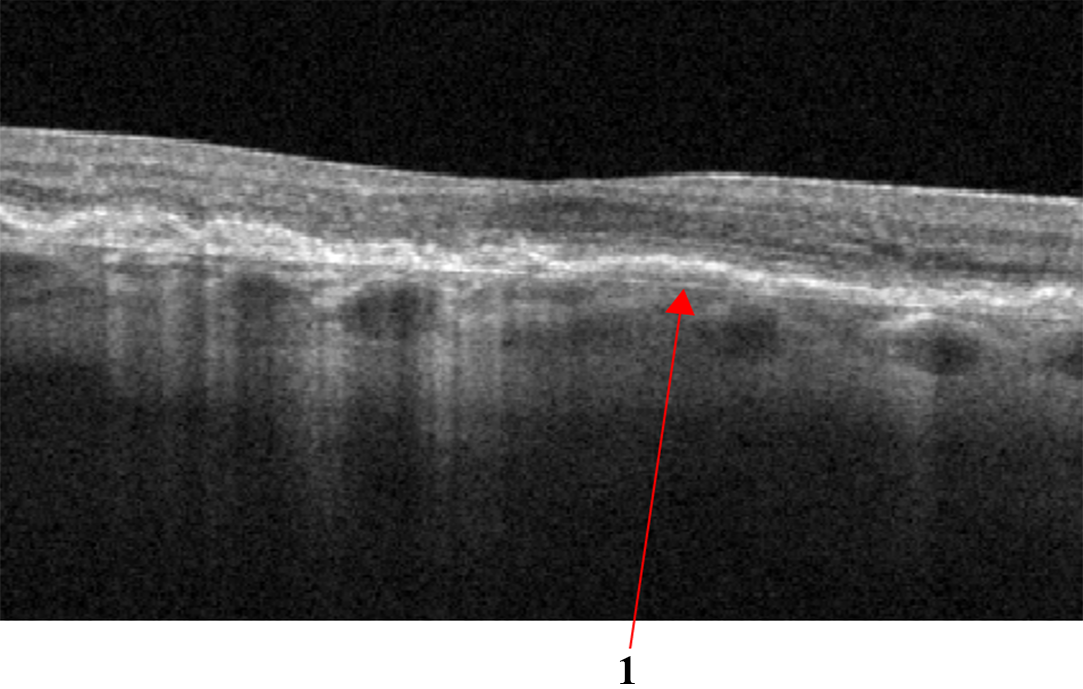

DRIL is an OCT biomarker, indicating poor definition of the boundaries of the inner retinal layers - in Fig.4b, DRIL is indicated by number 1. DRIL occurs in patients with various retinal vascular diseases with prolonged presence of intraretinal fluid, such as DME, or following a vascular occlusion, such as RVO. The degree of DRIL indicates the severity of the disease and correlates with the patient’s visual acuity prognosis. DRIL may persist even after the resolution of edema following treatment or in advanced stages of the disease [34].

• Hard exudates (HE) are defined as deposits of hyperreflective material replacing retinal tissue without increasing the underlying retinal thickness, and are considered an unfavorable sign representing the break down of the inner blood-retinal barrier with the potential to reduce visual acuity - in Fig.4a is shown with number 1.

• Intraretinal fluid (IRF) appears as heterogeneous sized cavities with hyporeflective content due to their fluid content; slight retinal thickening may indicate initial changes of fluid accumulation with focal retinal edema that may precede the appearance of multiple cystic spaces - in Fig.4a is shown with number 2.

Figure 4: (a) Signs of Diabetic Macular Edema (DME): 1 - Hard exudates (HE), 2 - Intraretinal fluid (IRF), 3 - Hyperreflective foci; (b) Disorganization of retinal inner layers (DRIL).